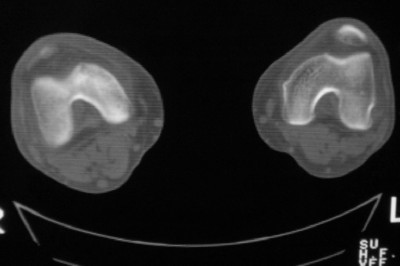

标题: CT8024:会诊!!!男 60 岁 双漆关节疼痛半年,进行性加重 [打印本页]

患者男 60 岁 双漆关节疼痛半年,进行性加重.

膝关节退行性变

右侧髁间隆突变尖,软骨下假囊肿形成,结合病人年龄较大,首先考虑退行性骨关节病。关节周围软组织未见明显异常,病人单单一双膝关节出现症状,不太支持类风湿性关节炎,可结合化验室检查。